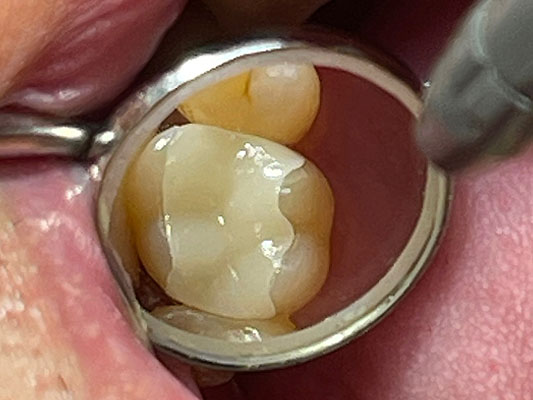

治療前

治療後

患者さんは50代の男性で、顎を動かして話したり食べたりする際、奥歯に過度の力や加わり、また上下の歯同士がぶつかることで、歯に負担がかかりその1本の歯だけでなく周囲の歯にも影響を及ぼしていました。そのため他医院で保険による銀歯の被せ物の治療を繰り返されていらっしゃったとのこです。今回は下顎の銀歯を白いセラミックで綺麗にしたいということで、恵比寿・広尾歯科に来院されました。お口のなかを拝見すると本来は顎が左右に動く際には犬歯が起点となって、奥歯に強い横向きの力が加わらないように隙間をつくるのですが、この患者さんは犬歯の働きが正しくできずに奥歯に強い力が加わり続けていました。この強い噛み合わせは歯周病の要因(咬合性外傷)となったり、周囲の歯をふくみ欠け・割れを引き起こすことがあります。根本原因を解決せずに白いセラミックで治療しても、固いセラミックにより反対側の歯を痛めてしまったり、時には固いセラミックも欠けるようなダメージを歯に受けることもあります。そこで根本的な噛み合わせと顎運動の改善から治療をスタートし、仮歯で時間をかけて患者さんの理想的な犬歯誘導が行われる形態と噛み合わせをつくり、最終的にセラミックの本歯で治療を終えました。